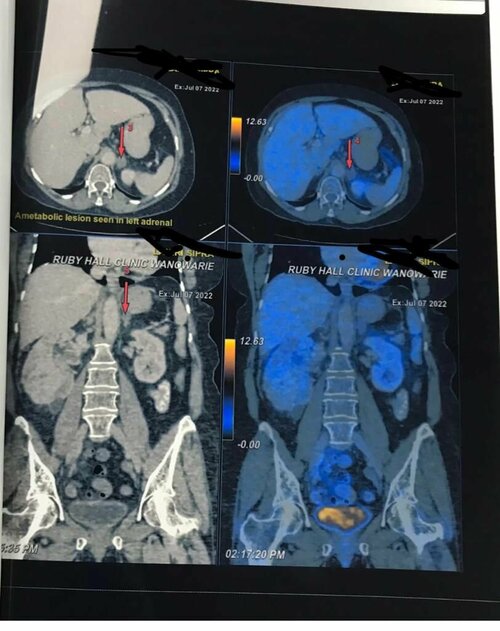

Robotic Radical Nephrectomy in Pune | Dr. Bhoopat Bhati | Urologist

A 68 years old woman visited Consultant Urologist in Pune, Dr. Bhoopat Bhati. She was having heavy bleeding in urine. It was painful for her. Dr. Bhoo...